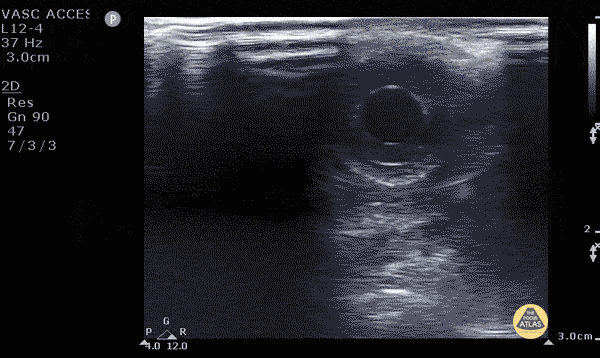

Name the sign

What is seagull sign

Bonus points 200: tell me the structures that compose it? ie arteries